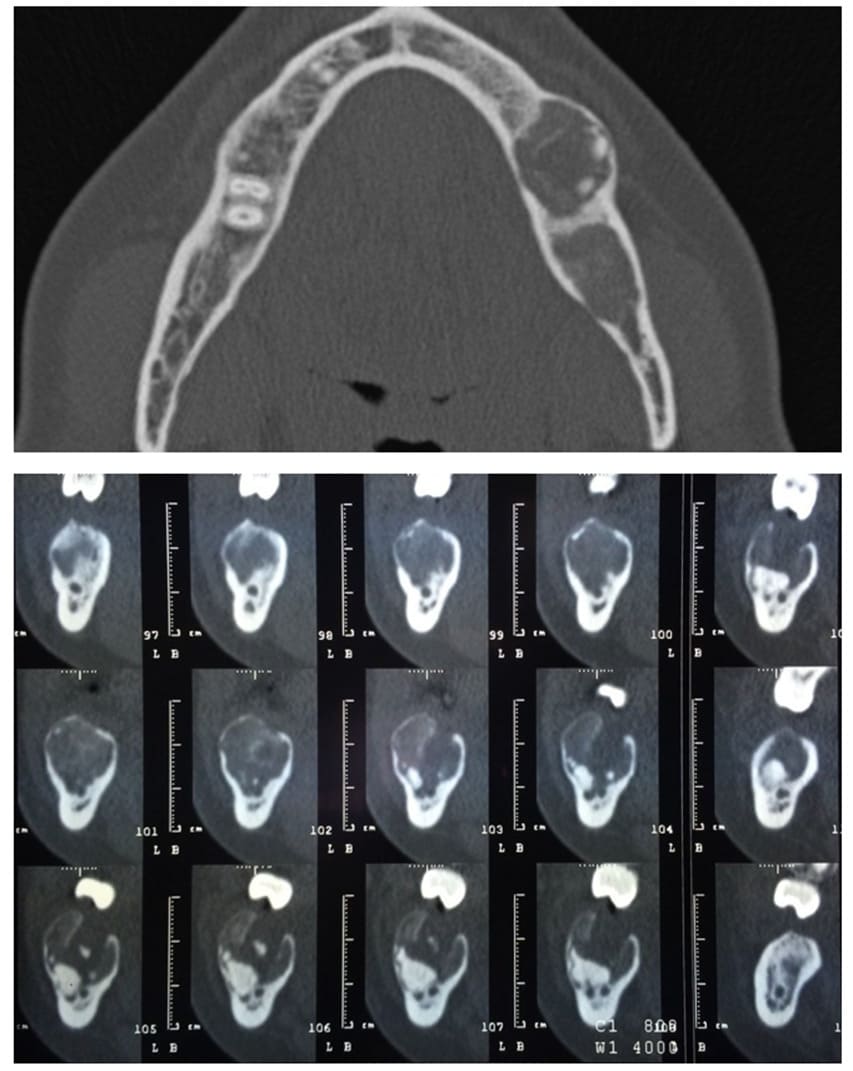

Case 2: a 52-year-old Brazilian female patient was referred to the Odontostomatology Department of Galliera Hospital in Genoa, Italy, with an asymptomatic deformation of the edentulous left posterior mandible (Fig. 8). The OPT revealed an irregular radiopacity in a poorly defined radiolucent area with a cystic appearance. Subsequent CBCT revealed a 20x15x15 mm osteolytic round lesion adjacent to the inferior alveolar canal, exhibiting bifurcation in correspondence with the radiodense mass, indicative of an impacted tooth. Posterior to this radiopacity, a smaller lesion was observed, involving the mandibular ramus (Fig. 6-7).

Figure 6-7: pre-operative CBCT scan, the upper transverse section shows the affected mandibular area. In the lower sagittal sections it’s also visible the affected area with the presence of an impacted tooth and the bifurcation of the inferior alveolar nerve.